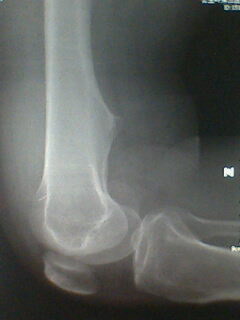

标题: X5658:膝关节改变?!

中年男性,外伤,疼痛!

股骨下段骨软骨瘤。撕脱性骨折

支持考虑骨软骨瘤,髁上突在肱骨内髁上方.本例股骨外髁关节面似有异常,但是可以是与髌骨重叠构成,必要时加照正位(稍内斜一点把髌骨让开)

宽基底与股骨干相连,背离关节面,支持考虑股骨下段外生骨疣

髌骨向外下移位,股骨下段骨软骨瘤。

宽基,无指状突起,考虑外生骨疣。